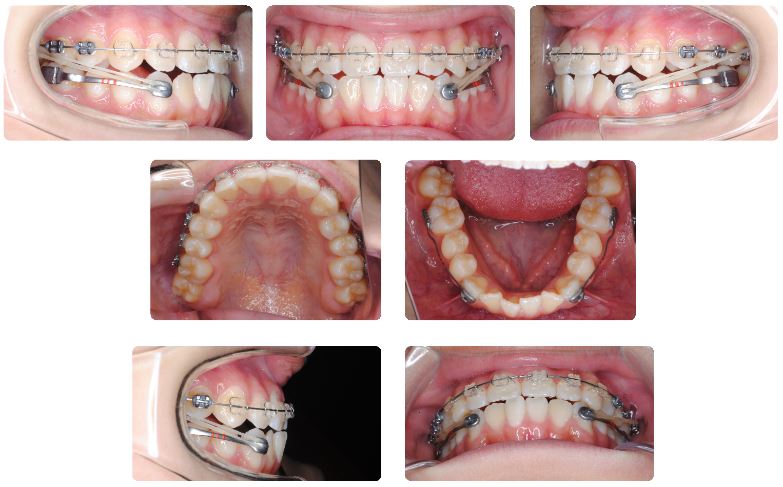

下顎側方歯にカリエールモーションを装着した直後の状態です。

カリエールモーション装着から3か月後です。

上顎前歯にみられるスペースは依然認められますが、上顎前歯の突き上げ感が改善されてきています。

下顎左側のカリエールモーションの後ろが脱離していますが、すぐに再装着しました。